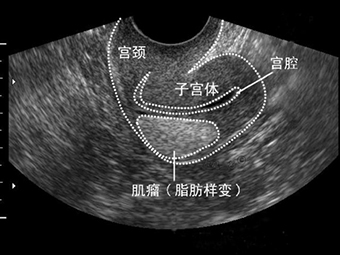

2 子宫肌瘤 不是一切了之

子宫肌瘤有女性生殖健康的“潜在杀手”之称。每3个女性中就有一个子宫肌瘤患者。子宫肌瘤是女性子宫体上长了肌瘤,也被称为子宫平滑肌瘤,是女性生殖器官最常见的良性肿瘤。预防子宫肌瘤,要求妇女在经期及产后要特别关注,严禁房事,保持外阴和阴道清洁,心情舒畅,减轻压力,关注保暖,禁止饮用生水,饮食宜清淡,易消化,忌食辛辣生冷刺激性食物,保持正气充足气血顺畅。

很多女性得了子宫肌瘤,见到医生第一句话就是,给我切了吧。其实不然,治疗子宫肌瘤的方法要视具体情况而定,并非一“切”解千愁。症状轻的患者,若子宫大小不超过孕12周的大小,则不必手术,只要每3个月去医院复查一次,随时关注肌瘤的变化即可。特别是对于近绝经期的患者,因其绝经后肌瘤有自然萎缩的可能,所以一般都主张保守治疗。